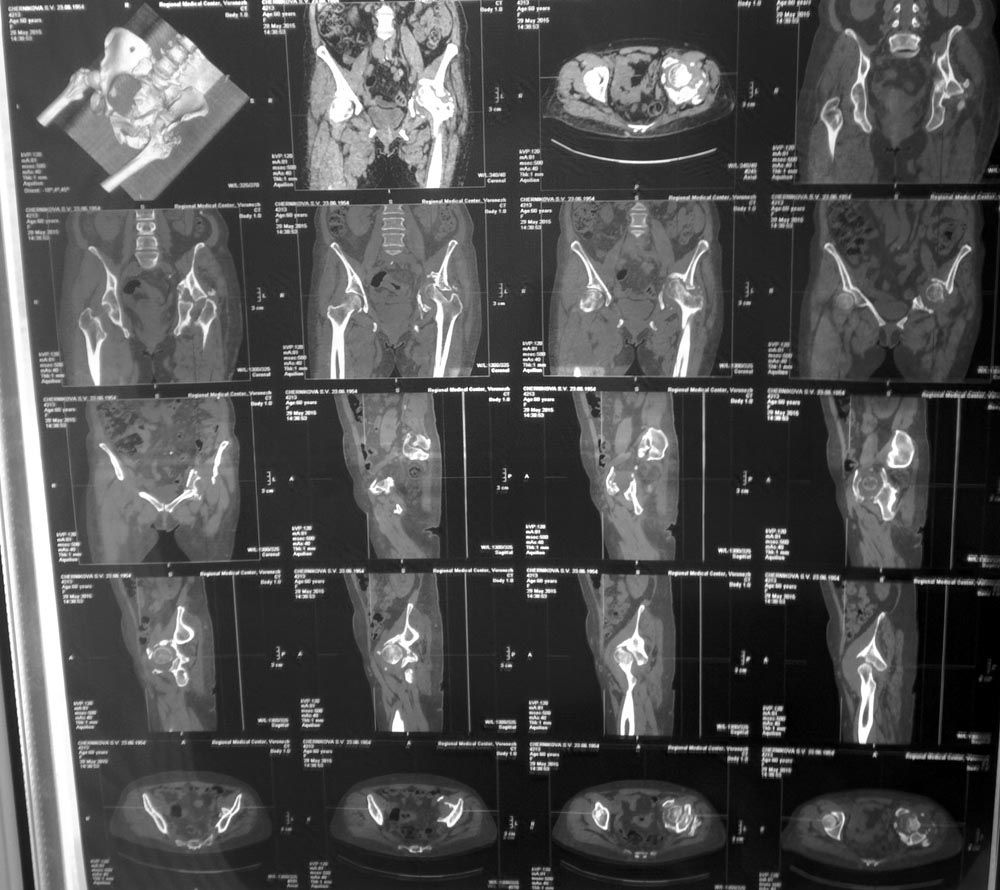

Женщина, 62 г, ДТП 25.11.2014. Перелом ВВ, лонной и седалищной костей с нарушением непрерывности тазового кольца, частичный разрыв КПС, гнойная рана бедра, все слева. Лечилась консервативно, вытяжение не удалось, полное заживление раны через 5 мес. Левая конечность неопороспособна, но явных признаков некроза головки нет. Пытаться выполнить остеосинтез при сроках 8 месяцев абсолютно нецелесообразно? Если неизбежно эндопротезировать, то поделитесь мнениями о предпочтительной тактике: как лучше поступить с передней колонной, сделать пластику ВВ аутокостью, необходимо ли кольцо Бурш-Шнайдера/Октопус?

Перелом похож на Т-образный или anterior column posterior hemi-transverse. Здесь передная стенка отошла на несколько сантиметров и с этим нарушено целостность кольца в вертлужной впадине. Небольшие смещения в задней колонне или в стенке, которых можно фиксировать во время протезирования, особых проблем не вызывают, а передная колонна-куда приходится основная нагрузка не выдерживает нагрузку и осложняются расшатыванием!

Усиливающее кольца Мюллера/Бурша-Шнайдера в основном сидит в задней колонне, а передная колонна остается свободной без опоры. В большинстве реконструкцонные специалисты обращают внимание на правила "вначале создание непрерывности кольца", которое влияет на долговечность артропластики.

Но, в данном варианте, еще имеется неполный разрыв крестцово-подвздошного сочленения и если не фиксировать, тогда возможно возникновение болей после артропластики и тогда трудно дифференцировать источник: из сустава или из крестцово-подвздошного сочленения?

По моему, гарантировать успех можно после профилактической фиксации КП сочленения и после создания стабильности передней колонны. Некоторые, после стабилизации вертлужной впадины чувствует намного лучше, и при конгруентной головке, возможно нет смысла спешить с заменой сустава? А операция в колонне дасть возможность оценить качество покрытия хрящом головки бедра и решить вопрос, замена сустава одномоментно или поэтапно!

Надо в первую очередь определиться со стабильность отломков - если они фиксированы, то заполнить дефекты головкой и поставить укрепляющее кольцо ЭСИ с тремя опорными ножками.

Бурш-Шнайдер здесь не очень - нет опоры и нет передней стенки.

на мой взгляд, необходимо стабилизировать тазовое кольцо (Stoppa, подвздошно-паховый), я бы сделал с сеткой и большим количеством аллографта - bone stock! При возможном последующем ТНА, что вероятно, выбор ацетабулярного компонента будет больше, вплоть до первичной чашки. на счет стабилизации КПС - не уверен, хотя из подвздошного доступа можно и там вмешаться с целью артродеза - будет надежнее. В условиях нестабильности тазового кольца результат артропластики будет плохо прогнозируемым. Следуйте рекомендациям Джолдаса Кульджанова, плохого он не посоветует.